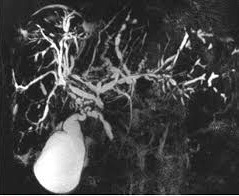

✅ Магнитно-резонансная холангиопанкреатография (МРХПГ) позволяет оценить внутрипеченочные и внепеченочные желчные протоки, а также протоки поджелудочной железы. Не уступает ЭРХПГ в качестве визуализации желчных протоков, при этом является неинвазивным методом с низким риском осложнений. МРХПГ не позволяет качественно визуализировать дистальную часть общего желчного протока из-за выпадения сигнала в проекции сфинктера Одди.